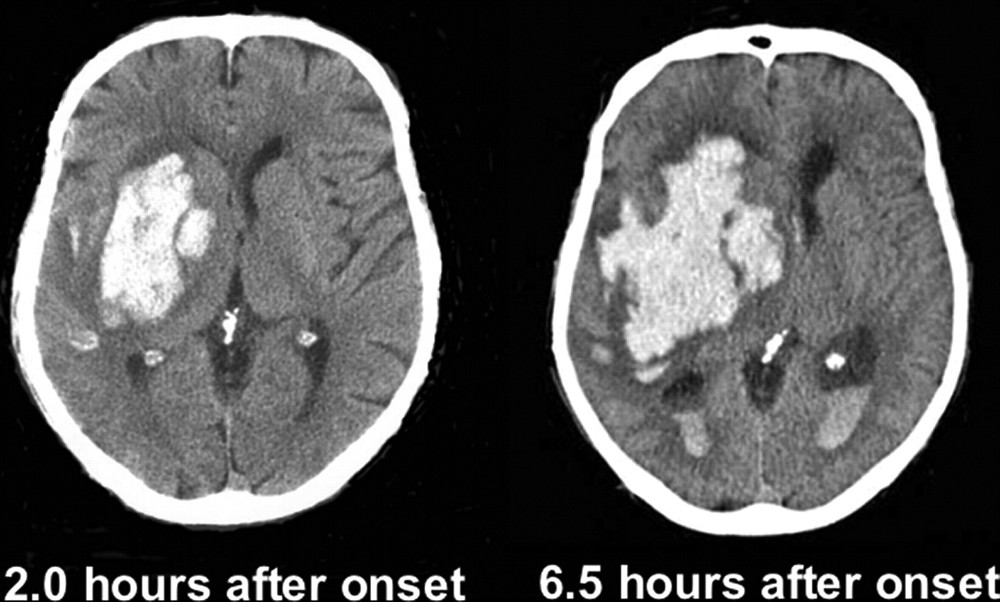

뇌출혈은 뇌 혈관이 파열되어서 발생하는 출혈을 의미합니다. 외상이나 심혈관 질환 등이 원인이 될 수 있습니다. 뇌출혈은 일반적으로 심각한 상태이며, 즉각적인 응급 조치가 필요합니다.